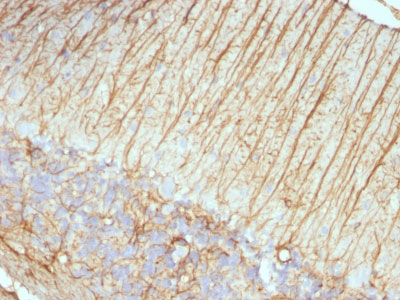

Formalin-fixed, paraffin-embedded human Cerebellum stained with GFAP Monoclonal Antibody (ASTRO/789).